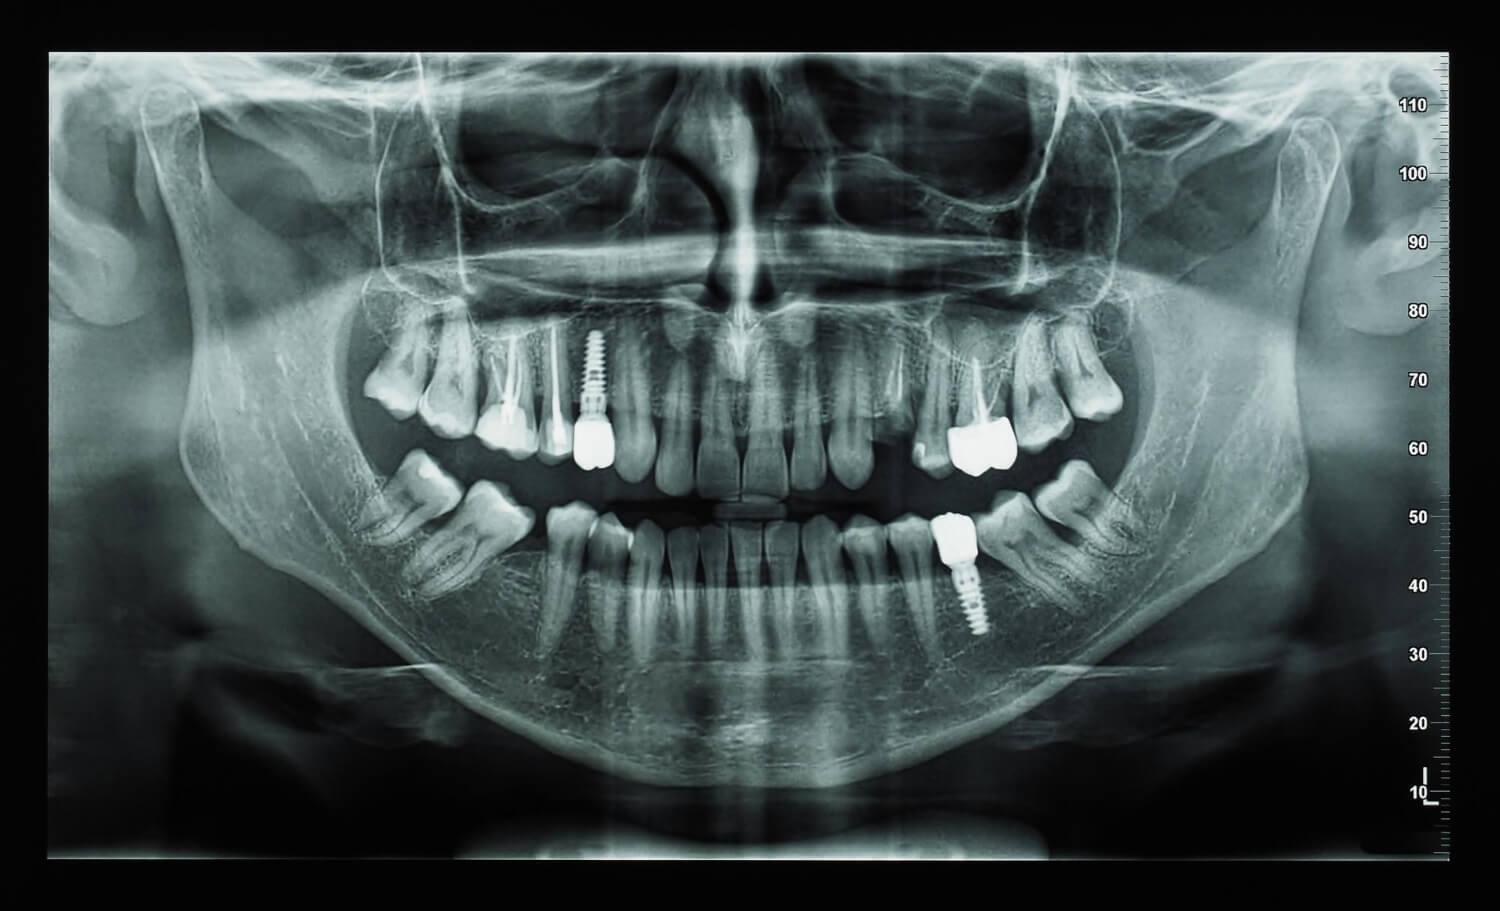

2D снимок

Панорамный снимок иначе называют ортопантомограммой (ОПТГ).Изучая ОПТГ, можно оценить состояние обеих челюстей в формате 2D, а также провести оценку отдельных зубов, костной ткани, гайморовых пазух.

Панорамный снимок назначается при:

• патологиях прикуса;

• воспалениях, локализованных в рядом расположенных зубах;

• амелобластоме;

• переломе нижней челюсти;

• остеомиелите;

• для диагностики ретированных зубов: которые не прорезались либо расположены неправильно;

• атрофических изменениях костной ткани;

• при планировании ортопедического, ортодонтического лечения.

Процедура простая и безопасная для пациента, занимает около 15 минут вместе с получением результата. Выполняется на оборудовании, которое называется ортопантомограф. Перед снимком пациенту нужно сжать губами пластину из пластика. Во время диагностики датчик движется вокруг головы пациента и продуцирует рентгеновские лучи. Тело и голова защищаются от излучения. Полученное изображение сохраняется на диске, карте памяти.

Среди недостатков данного вида диагностики следует отметить:

• некорректную передачу размера анатомических структур до 15-30 %;

• неинформативность при диагностике зубов, имеющих три корня (они находятся в 3 разных плоскостях, тогда как ортопантомограф дает двухмерную картинку);

• плоское, а не объемное изображение.